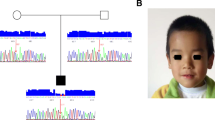

Whole exome sequencing identified one variant (c.1626 + 1G > A) in AHI1 (NM_001134832.1) and two variants (c.1147delC and c.1054A > G) in PIBF1 (NM_006346.2) in a heterozygous state in the affected individual. Direct Sanger sequencing of the patient and parents showed that AHI1 c.1626 + 1G > A was from his father (heterozygote) as his mother was wild-type for this variant. For PIBF1, only one heterozygote of these two variants was observed in his parents (c.1147delC in mother and c.1054A > G in father) (Fig. 2).

Sanger chromatograms. a c.1147delC variant in PIBF1 in a heterozygous state in the proband (upper panel) and a heterozygous state in the mother (middle panel) and a wild-type homozygous state in the father (lower panel). b c.1054A > G variant in PIBF1 in a heterozygous state in the proband (upper panel) and a wild-type homozygous state in the mother (middle panel) and a heterozygous state in the father (lower panel). c c.1626 + 1G > A variant in AHI1 in a heterozygous state in the proband (upper panel) and a wild-type homozygous state in the mother (middle panel) and a heterozygous state in the father (lower panel)